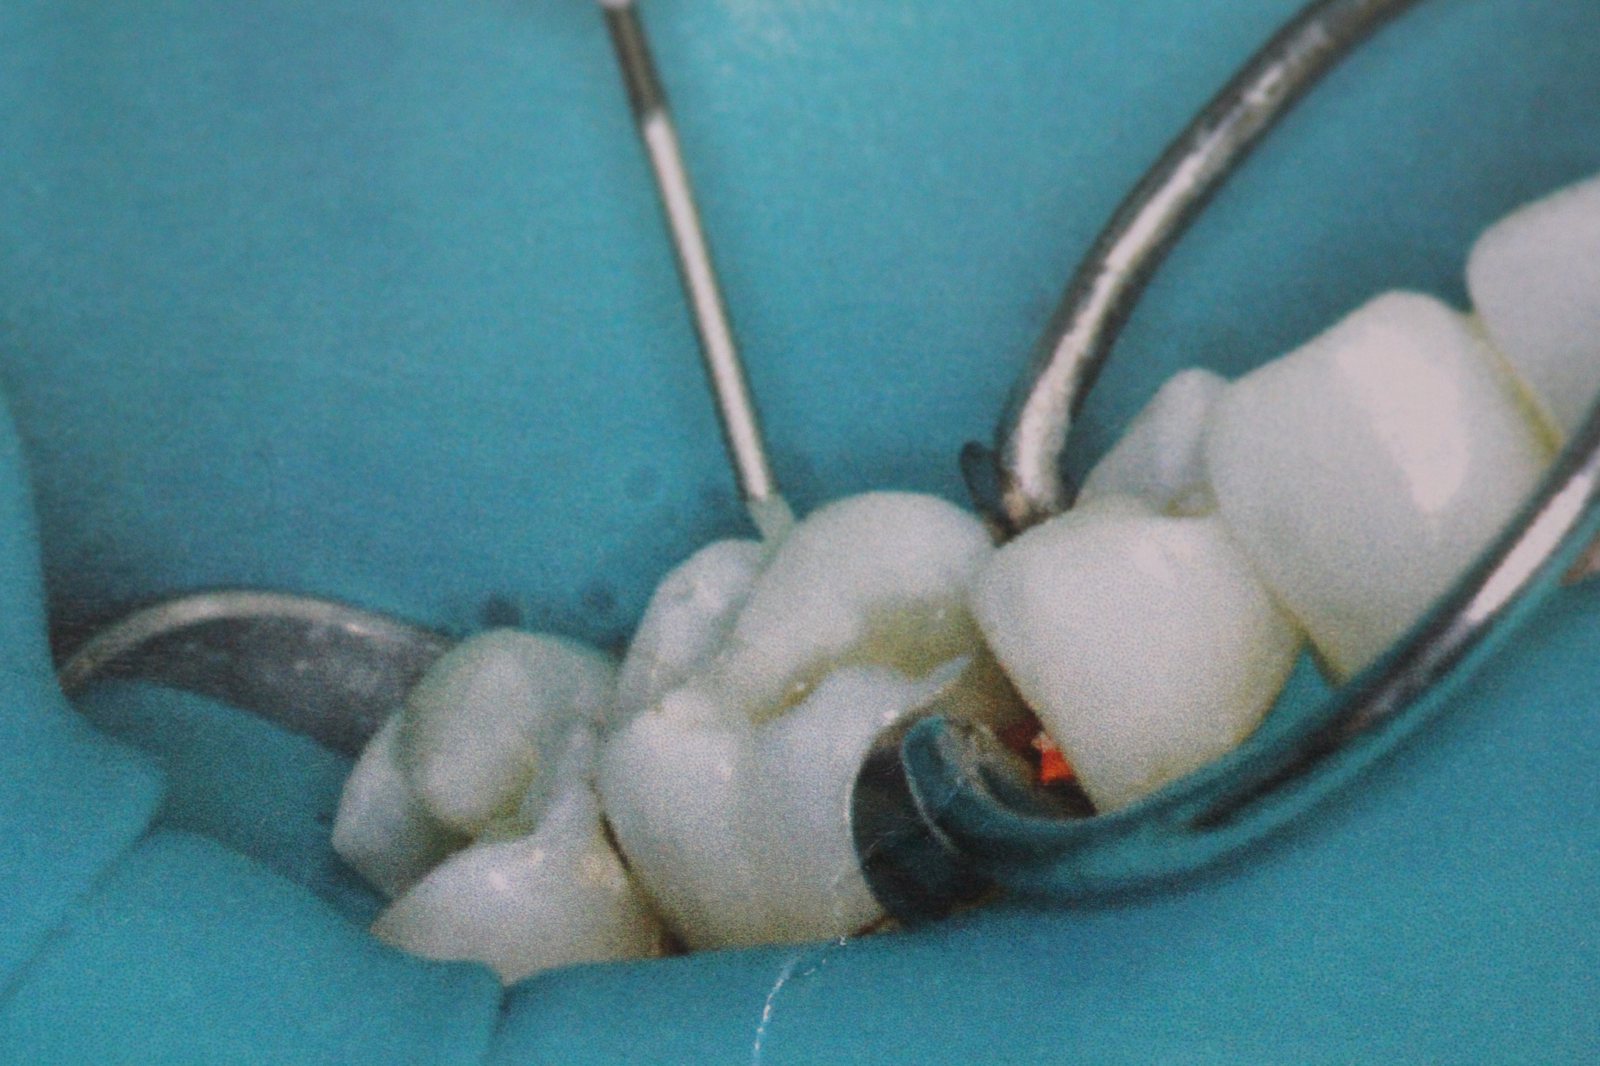

Primer vsakdanjega postopka v ordinacijah, kjer je postopek menjave amalgamske plombe skrajšan in kvaliteten z uporabo bulk tehnike: